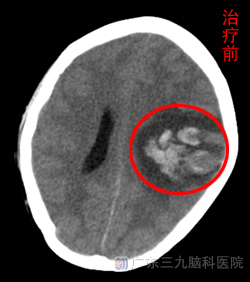

12月1日,肖女士无明显诱因出现头痛,3天后头痛逐步加重并伴有右侧肢体麻木无力,于2012年12月7日6:57时来院就诊。曾到当地医院就诊,头部检查示左侧顶叶出血,予以脱水、营养等药物治疗后症状未见减轻,并逐步出现意识模糊、发热,为求进一步诊治而转入广东三九脑科医院。

入院查体:体温38℃。嗜睡,完全运动性失语,查体不合作,双侧瞳孔等大同圆,直径:3mm,直接、间接对光反射正常,右侧肢体肌力0-1级,肌张力正常,右侧肢体痛温觉、触觉均减退,右侧腱反射活跃,右下肢Babinski征、Chaddock征均阳性。颈项强直,Kernig征、Brudzinski征均阳性。既往史:2年前妊娠后月经增多,行妇科检查发现子宫肌腺给予孕激素(避孕药)治疗2年。www.999brain.com

入院当日行头颅CTA示左侧额顶叶出血(亚急性期),颅内未见明确动脉瘤及畸形血管征象。外院MRV及我院CTA均不能确定是静脉还是动脉出血。于12月11日行DSA检查显示:左侧横窦、乙状窦血栓形成,动脉期血管未见明显异常。检查后确定为静脉血栓形成引起脑出血,给予足量、长疗程低分子肝素钙抗凝,经治疗1周后患者意识转清,D-二聚体(D-dimer)2.7mg/L。治疗1个月患者言语恢复流利,右侧肢体能抬离床面,复查头颅CT示现左侧额顶叶内出血及水肿较前有吸收,占位效应较前减轻(见对比图)。www.999brain.com